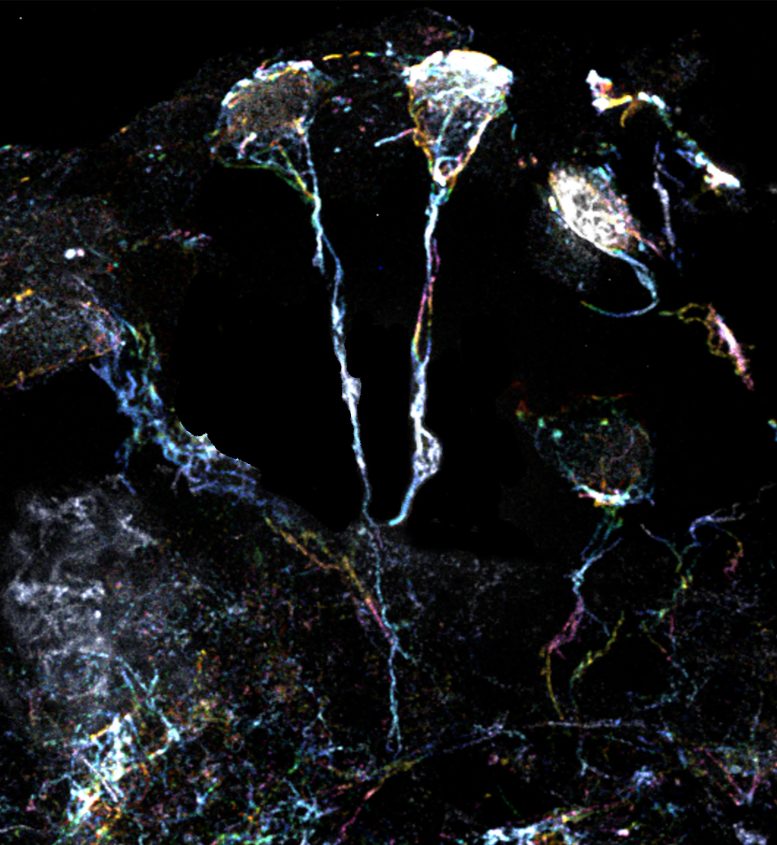

科學家團隊使用放大倍數為10倍的超分辨率顯微鏡檢查了果蠅休眠神經干細胞的標志性微小纖維結構。這些細微結構的直徑約為1.5μm(比人類頭發的直徑小20倍),是從細胞體延伸出來的突起,富含肌動蛋白或蛋白質細絲。一種特定類型的Formin蛋白可以激活這些細絲并使其組裝。

科學家們觀察到,星形膠質細胞會釋放一種名為“折疊原腸胚形成”或“Fog”的信號蛋白,這種蛋白會引發連鎖反應,包括激活Formin蛋白通路來控制肌動蛋白絲的運動。最終,這些過程會喚醒神經干細胞,使其脫離休眠狀態。然后,它們開始分裂,產生有助于大腦修復和發育的新神經元。